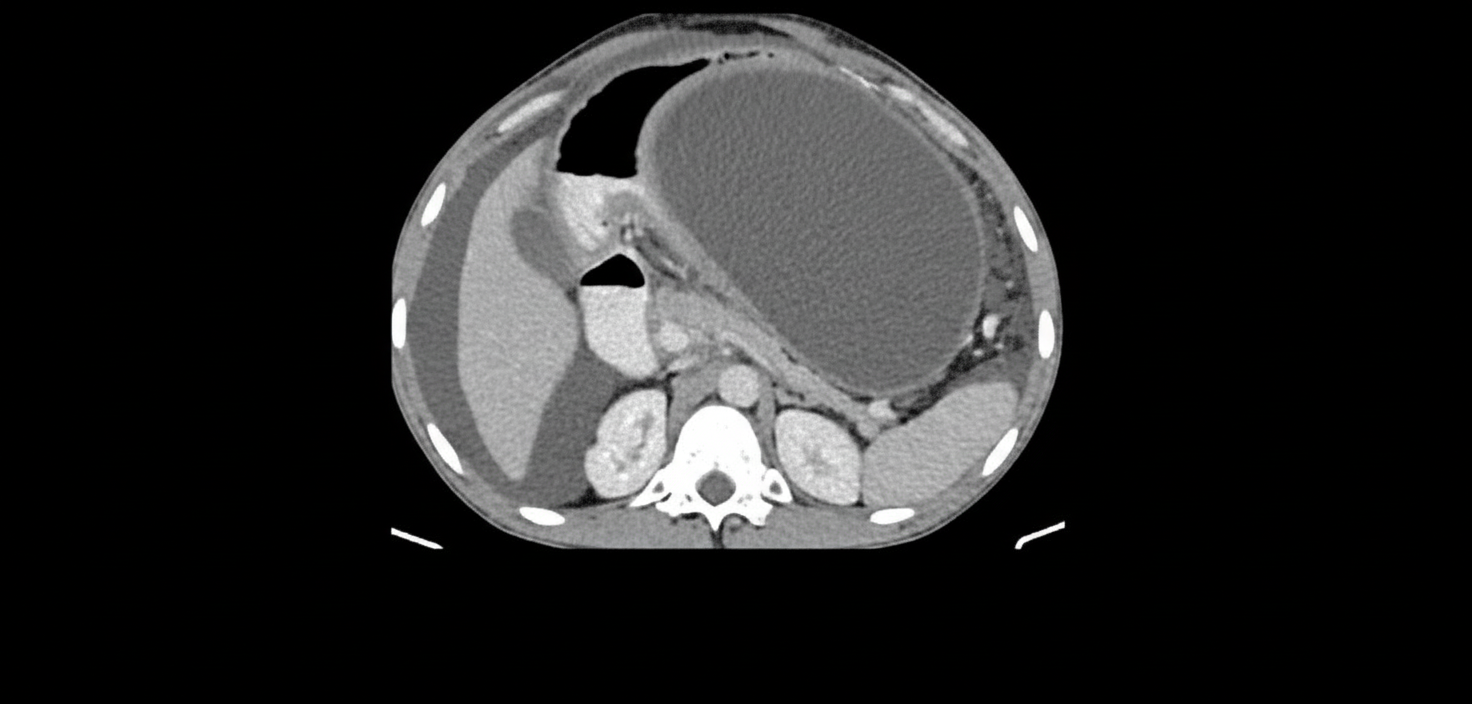

A 30-year-old patient presents with severe upper abdominal pain and elevated serum lipase. A CECT scan was performed and is shown. What is the next line of management?

Explanation: ***Internal drainage*** - **Large pancreatic pseudocysts** (>6 cm) that are symptomatic require **internal drainage** via **cystogastrostomy** or **cystojejunostomy** to create permanent communication with the GI tract. - This approach provides **definitive treatment** with lower recurrence rates and avoids the complications associated with external drainage systems. *Conservative management* - Reserved for **small, asymptomatic pseudocysts** (<6 cm) that may resolve spontaneously over time. - **Large symptomatic pseudocysts** like this case require active intervention due to risk of complications like **rupture**, **infection**, or **biliary obstruction**. *External drainage* - Primarily indicated for **infected pancreatic collections** or **necrotizing pancreatitis** with sepsis requiring immediate drainage. - Results in **high recurrence rates** and potential for **pancreaticocutaneous fistula** formation, making it suboptimal for sterile pseudocysts. *Endoscopic retrograde cholangiopancreatography (ERCP)* - Useful for **pancreatic duct strictures** or **stones** but not the primary treatment for **mature pseudocysts**. - May be considered if there is associated **pancreatic duct disruption** or **biliary obstruction**, but internal drainage remains the definitive management.